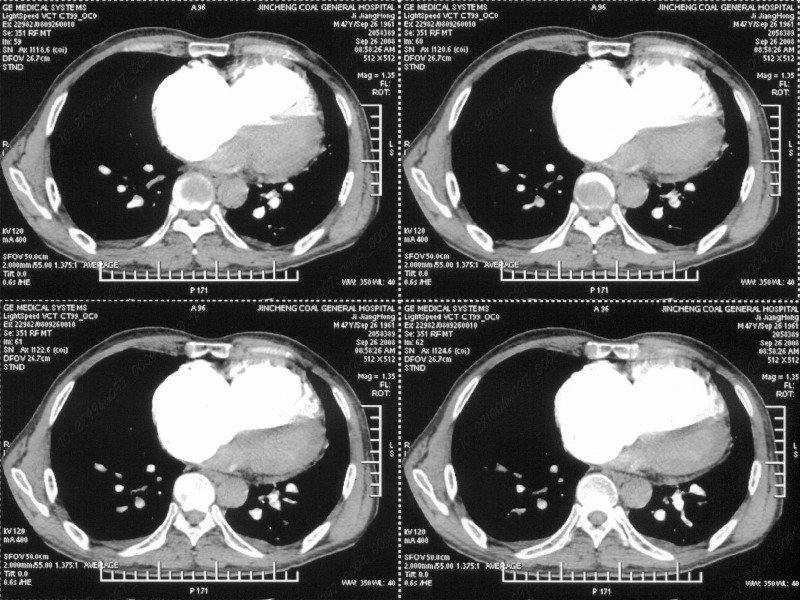

男性,47岁。胸部不适一年,ct检查发现右胸膜下结节。http://www.radida.com/bbs/forum.php?mod=viewthread&tid=46094

图像很清,资料很全。工作做的很细,向您学习!观阁下的强化图像发现,您们强化后扫描时间挺早,延迟时间大约在16—18秒之间吧。估计目的是为了观察肺动脉及分支的情况。但现有的资料并不能提示动脉栓塞改变。建议楼主可在机器上仔细观察,或许会有异常发现。另外,个人感觉右侧应为肺内结节而非胸膜结节。考虑肺内良性小结节,炎性假瘤可能性大。

病灶周围似有纤维化征像,增强明显强化,但中央可见点状低强化区,考虑慢性病变可能如炎性假瘤等,病灶边缘部分毛糙有切迹,双侧胸腔少量积液影,不除外恶性

结节未见明显强化,局部胸膜增后粘连,内缘纹理影增重伴小围星灶,局部胸膜下小三角状实变影,尖端见纤维索牵扯征,综合考虑炎性病变,有增殖表现,不出外tb灶

右肺静脉充盈缺损,左心房体积小,右肺动脉远端动脉充盈缺损,右肺血管影细小,考虑;右肺动脉远端栓塞.